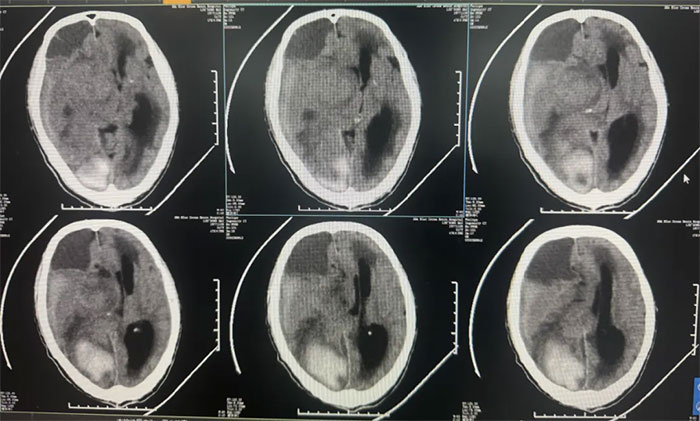

上海蓝十字脑科医院|长时程外引流在神外脑脊液管理应用病例分享一例和思考

上海蓝十字脑科医院卢云鶴副主任医师带来的:长时程外引流在神外脑脊液管理应用病例分享一例和思考...【详细】